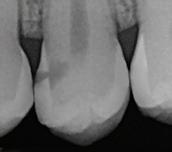

In the endodontic stage, conservative endodontic preparation and obturation with modern techniques are performed as they are for any tooth. All endodontic procedures are performed under an operating microscope to maximize visualization and illumination of the fracture line (Fig 1). The coronal portion of the newly placed gutta percha is removed 2 to 3 mm below the deepest extent of the crack in the affected canal to prepare for intraradicular barrier placement (Fig 2). Gutta percha is also removed 2 to 3 mm into the other noncracked canal orifices in the tooth to prepare for traditional orifice barriers. Microscopic transillumination with a fiber-optic light, in which an LED light probe is placed against buccal or lingual tissues overlying the roots, is utilized to illuminate the root and enhance visualization of the crack (Fig 3). A flowable resin-modified glassionomer or composite resin is then placed in this newly created void from the level of the gutta percha to the floor of the pulp chamber in all canal orifices (Fig 4). A composite resin core is then placed to permanently restore the endodontic access. If a temporary or permanent crown is not placed immediately after the endodontic procedures, the tooth is reduced

Periapical radiograph at the completion of the endodontic protocol. Resin-modified glass ionomer cement is placed as an intraradicular barrier in the distal canal, along the pulpal floor, and as an orifice barrier in the mesial canals.

Fig 2. Gutta percha removed 2 mm apical to the terminus of the fracture (arrows).